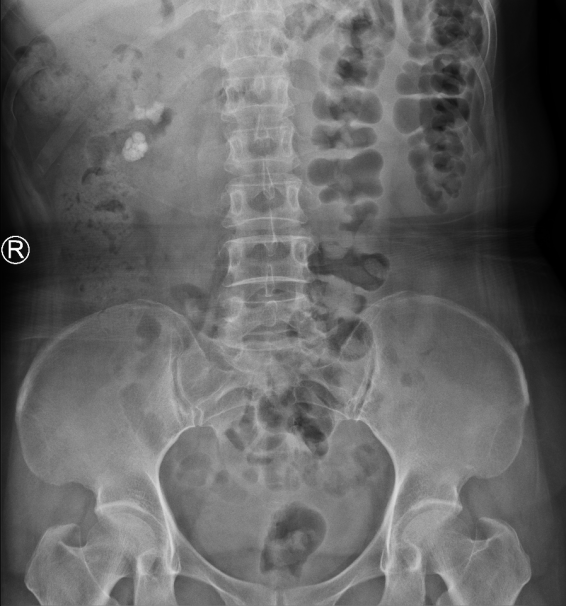

术后第二天吴女士就拔除了导尿管,体温正常,复查血、尿常规提示炎症指标都不高,同时,复查尿路平片发现结石清石率达到了100%,困扰了她许久的问题终于得到了解决。

术前术后尿路平片对比